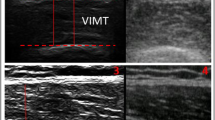

All US examinations were performed with a Siemens Acuson Aspen system using a 7.5 MHz linear transducer (38 mm width). The dynamic image was recorded digitally as cine-loops.

Muscle parameters measured with US

Limb lengths were measured using anatomical landmarks: underarm length, and the distances between the olecranon process of the ulna and the processus styloideus of the ulna. For measurement purposes, the live US images (cine-loops in the transverse and longitudinal planes) were reviewed and measurements were carried out on the still US image of the completely relaxed muscle, as well as the fully contracted muscle (live cine-loops). The optimal and standardized location for US measurements was a point distal from the origin of the EDC (the lateral epicondyle) corresponding to 15% of the total arm length (Fig. 3). This location exhibited the largest muscle area, which was clearly defined and thus easy to measure, and is referred to as the measuring point in the text.

US measuring point. (A) Position of the probe for ultrasound measurements of the EDC, 15% distal of the EDC origin. (B) Transverse US image obtained at the measurement position (contracted muscle). The circumference is shown by the dotted line, the cross-sectional area is the area within the line, and the muscle thickness is indicated by the double-headed arrow.

The pennation angle was defined as the angle created by the fascicles and the insertion into the deep aponeurosis. Longitudinal US images were recorded at 15% distal from the muscle origin, according to procedures described previously [2]. The pennation angle was measured as the angle between the muscle fibres and the deep aponeurosis of the insertion of the tendon when the fingers were extended (Fig. 4).

c) Contraction pattern

The contraction pattern was defined by two descriptors: the change in the shape of the muscle CSA (the relation between the length and diameter of the muscle) (Fig. 5), and the movement of the deep aponeurosis. Dynamic images were recorded at the measuring point in a transverse view to determine the change in muscle shape and the change in the position of the deep aponeurosis.

Three different approaches were taken to measure the distal insertion tendon position in the relaxed vs. the contracted muscle. Longitudinal and trans-sectional measurements at the level of the processus styloideus were evaluated (Fig. 6).